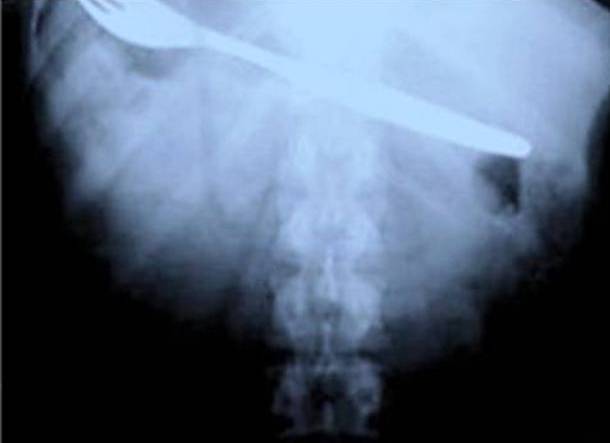

23. Swallowing A Spatula

It is amazing the things people do in moments of panic...and it seems from this list that it almost always leads to more problems. In this case, a woman was cooking in her kitchen, when she found herself unable to breathe properly. Then, she shoved a spatula down her throat. Did it help? Absolutely not. In fact, as we can see, this got stuck too.Advertisement